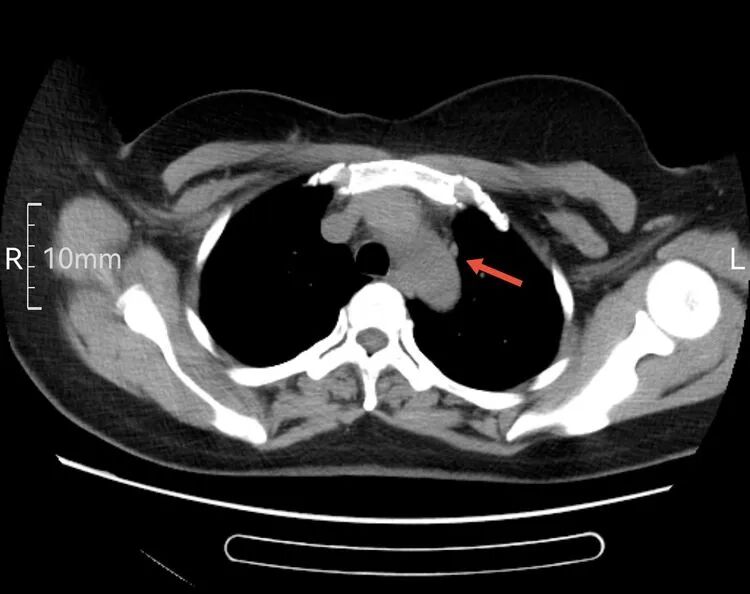

以下是患者的CT表现:

为什么建立双输液通道输液港 偶遇“双上腔静脉”_https://www.jmylbn.com_新闻资讯_第2张

箭头所指为左侧“上腔静脉”走行  虽然过程不寻常,但在血管造影辅助下显示其“真容”后,导管经左侧颈内静脉,避开变异的“左上腔静脉”并通过左侧头臂干,导管头端留置在正常的上腔静脉内。成功给予患者植入左侧胸壁港。